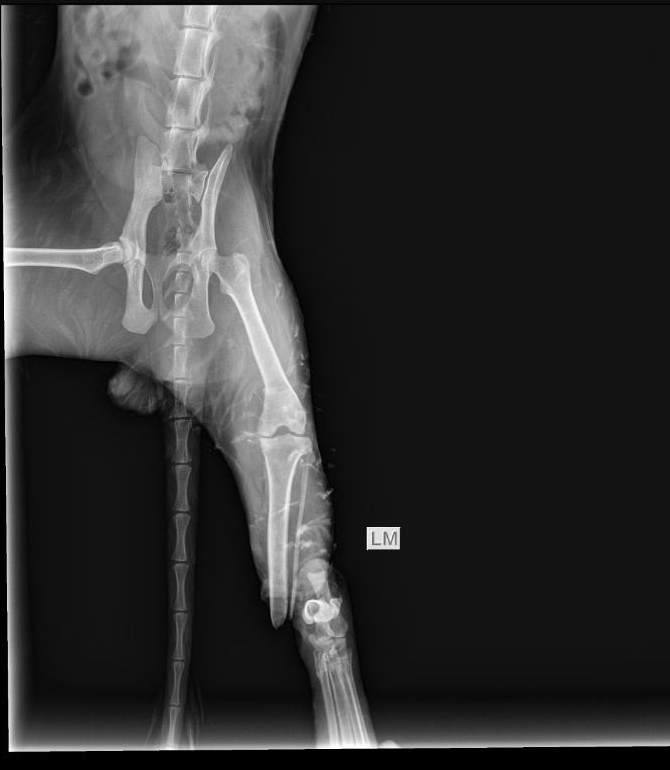

Экстренно!!! нас ждут в клинике, уличный кот, попал в капкан,котику очень больно,очень сильно кричит,нога болтается,открытый перелом берцовой кости.